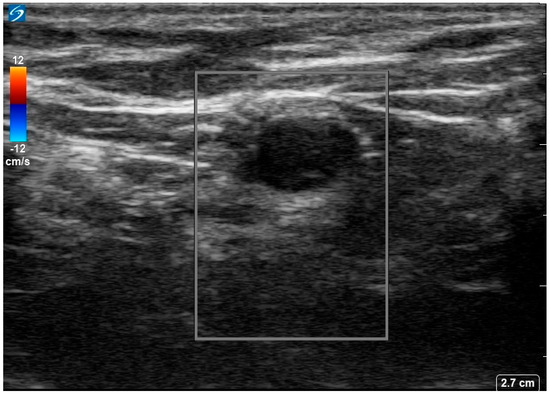

She was diagnosed with seronegative opsoclonus-myoclonus ataxia syndrome of paraneoplastic origin. Given suboptimal response to IVIG, she was started on 1 g IV methylprednisolone for 5 days. An ultrasound of the left axilla identified a 0.9 × 0.6 cm hypoechoic node with notable loss of the normal fatty hilum and reniform shape, irregular margins and prominent peripheral feeding vessels (Figure 2.

Figure 2.

Ultrasound image of the 18−FDG avid left axillary lymph node. Image shows a 0.9 × 0.6 × 0.7 cm markedly hypoechoic lesion with loss of normal fatty hilum, reniform shape, and irregular margins with prominent peripheral feeding vessels.